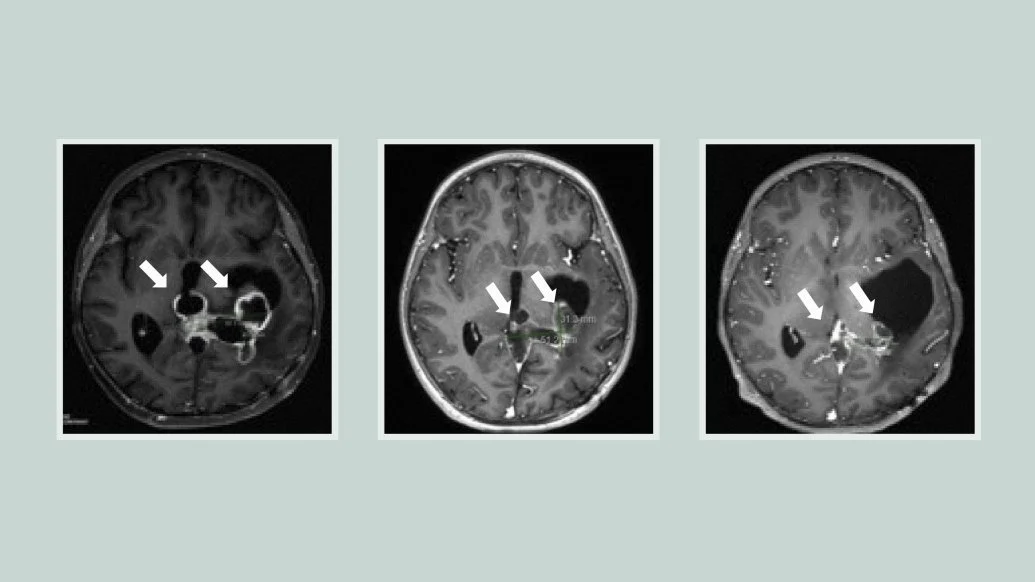

Progressive brain scans show the tumor responding to treatment with ONC201. Credit: Rogel Cancer Center

In two clinical trials testing ONC201 in a total of 71 patients with H3K27M-mutated diffuse midline gliomas, the median overall survival was nearly 22 months for tumors that had not recurred at the time of enrollment. Almost a third of the patients lived longer than two years.